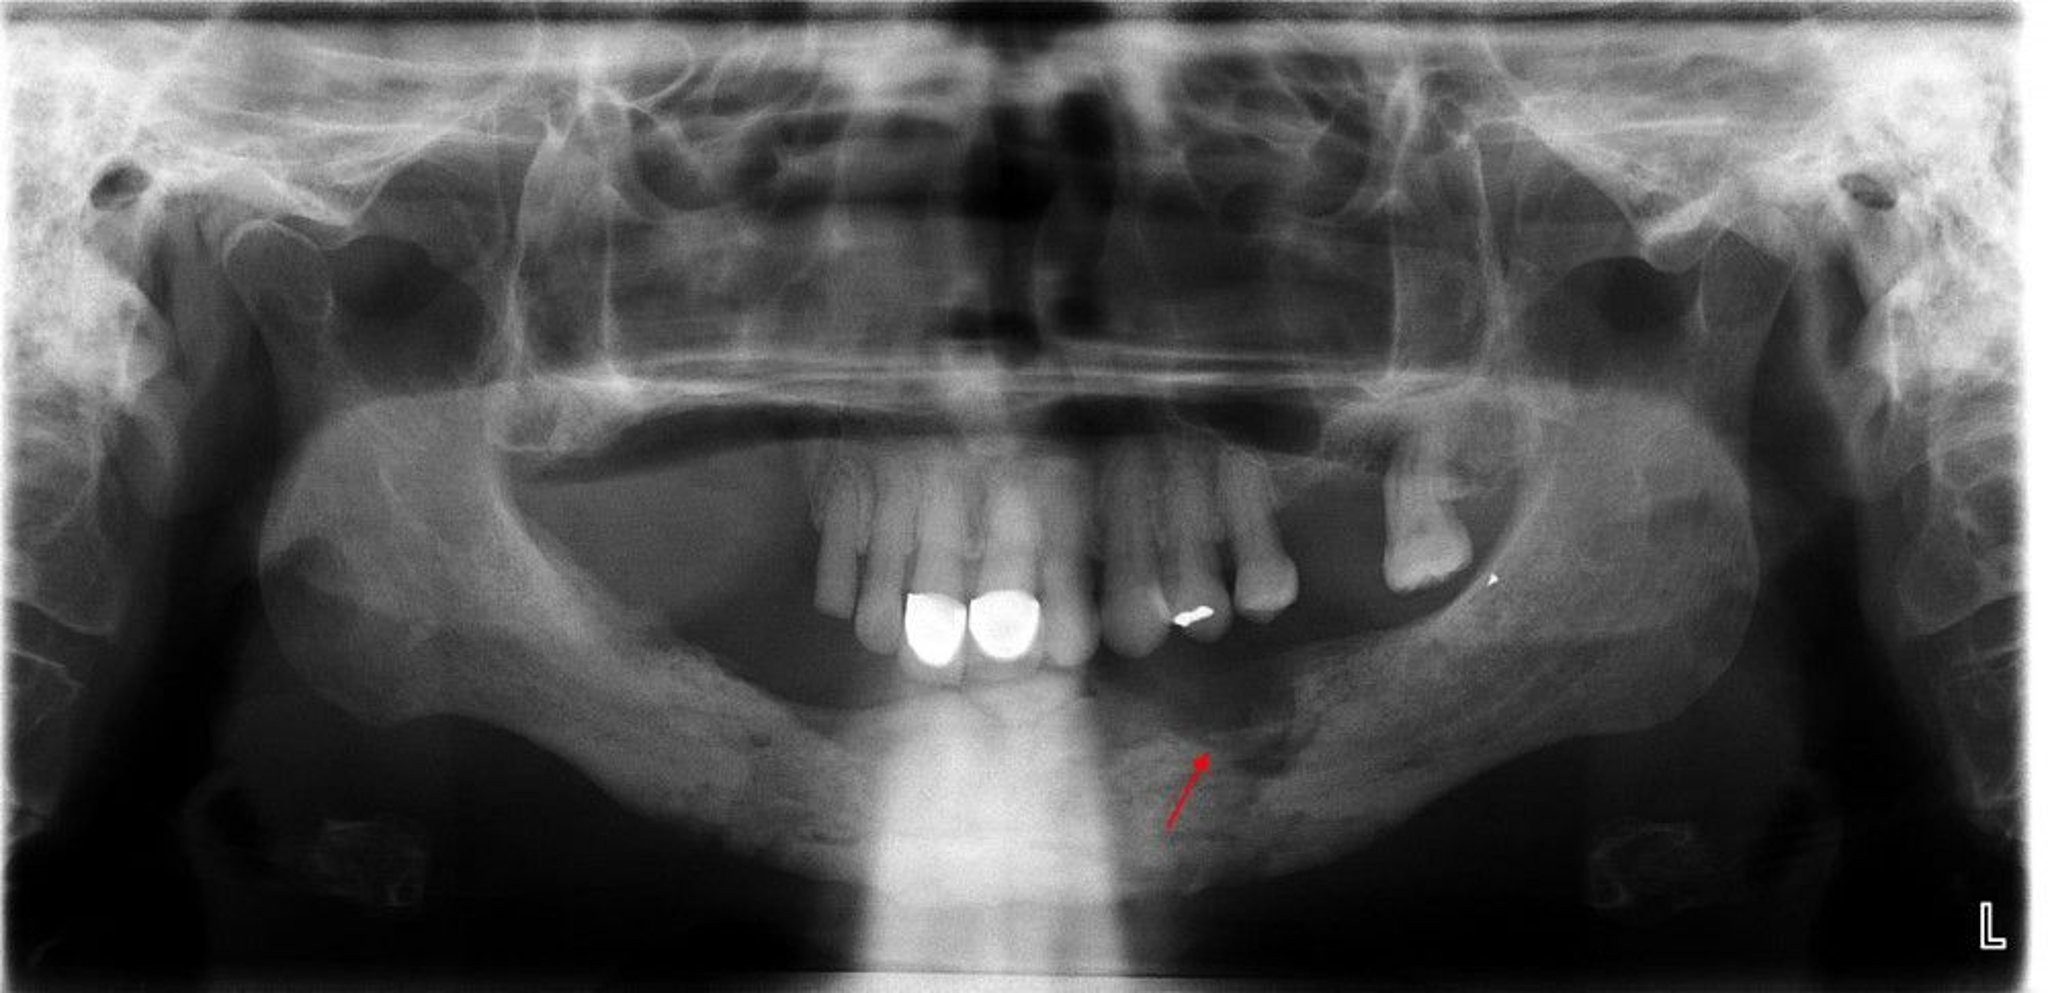

Diese Röntgenaufnahme zeigt eine Osteomyelitis mit einem deutlichen Sequestrum (nicht lebensfähiger Knochen) im linken Unterkieferquadranten (Pfeil).

Image courtesy of Byron (Pete) Benson, DDS, MS, Texas A&M University Baylor College of Dentistry.